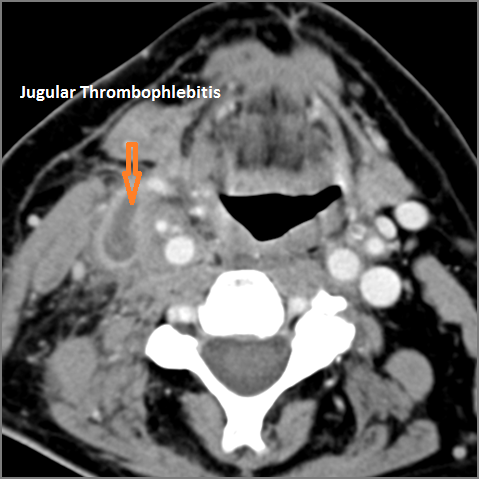

There is evidence of thrombus, thrombophlebitis or other occlusive or inflammatory process of the jugular vein or smaller venous tributaries.